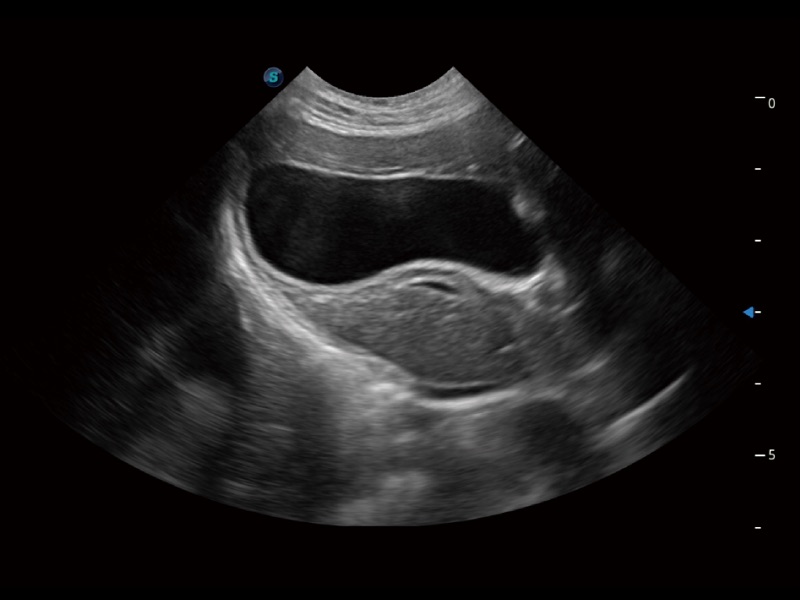

ProPet 70 进一步提升了微米成像算法,更加注重对基础原始图像的还原和保留,在有效减少斑点噪声、增强组织边界显示的同时,避免过度优化丟失真实的解剖信息。

ProPet 70专为动物医生设计,对不同的动物体型和生理结构作出了针对性的优化。通过动物影像专用软件,可满足个性化的应用需求,帮助动物医生获得更精确的诊断数据。

为精细结构及组织边缘提供高清晰度的图像和更大的成像视野。帮助减轻医生的用眼疲劳,快速精准获得测量的数据。